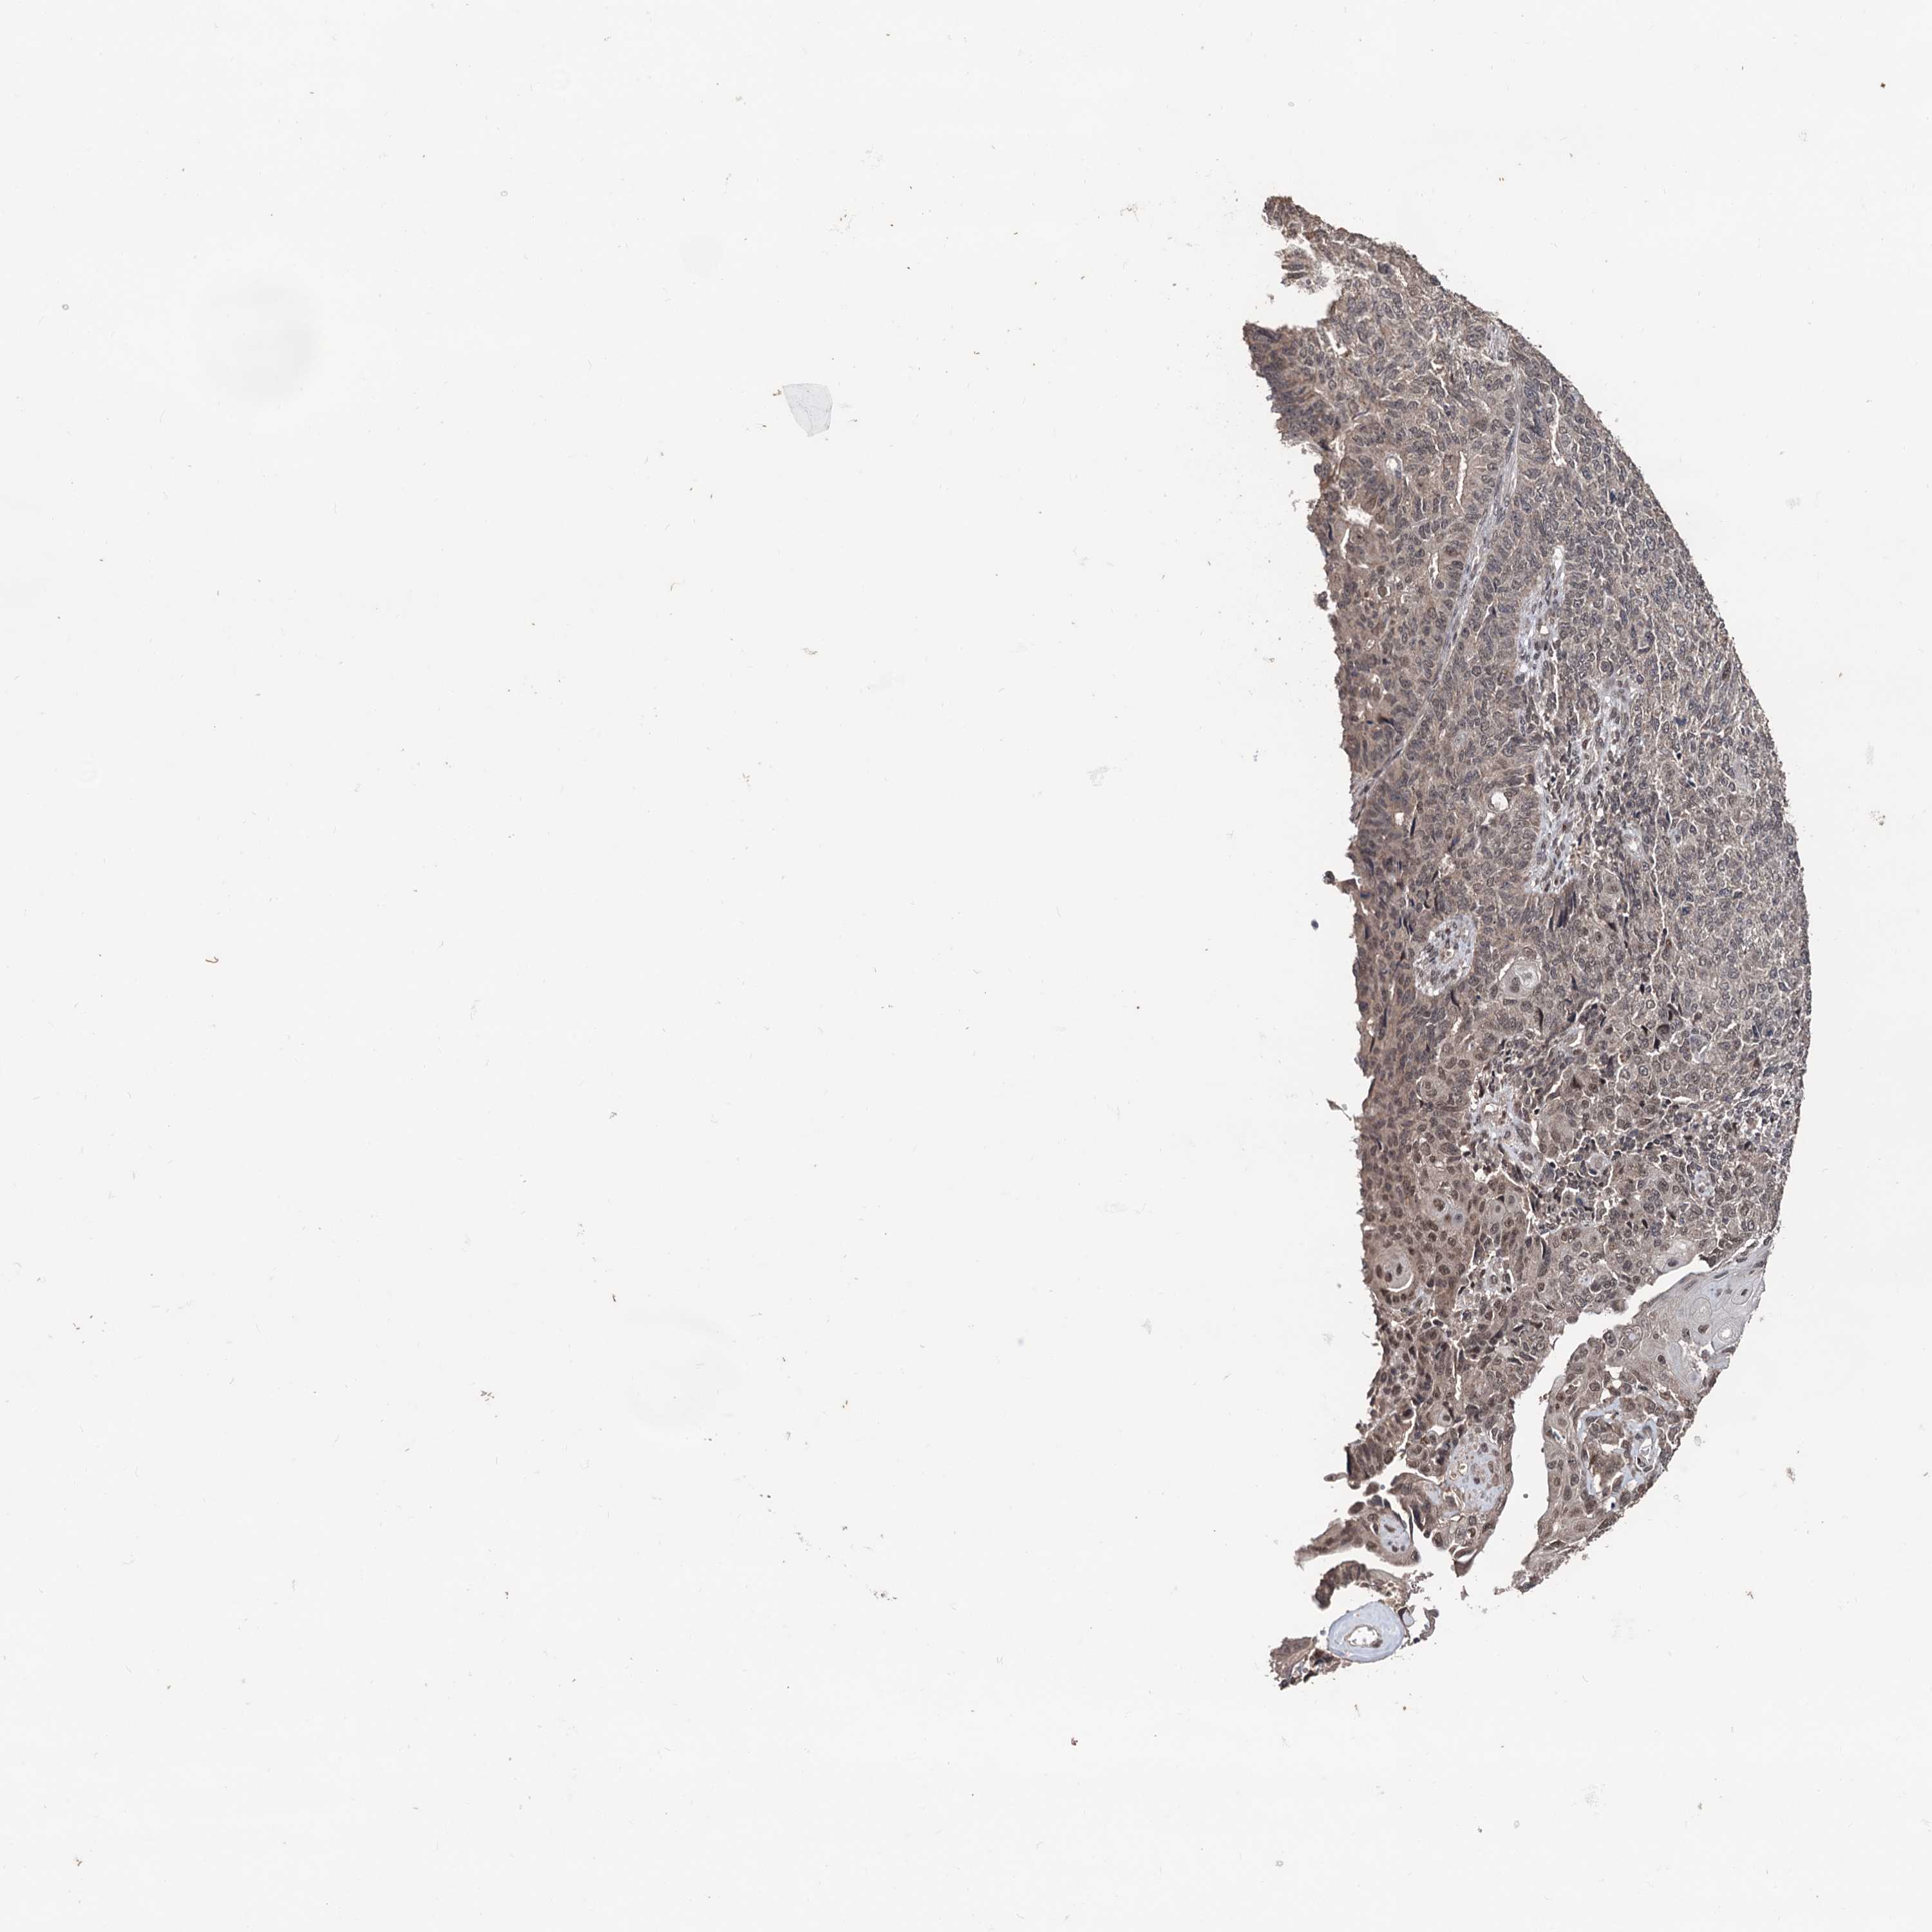

ENDOMETRIAL CANCER - Protein expressioni

A mouse-over function shows sample information and annotation data. Click on an image to view it in a full screen mode. Samples can be filtered based on level of antibody staining by selecting one or several of the following categories: high, medium, low and not detected. The assay and annotation is described here.

Note that samples used for immunohistochemistry by the Human Protein Atlas do not correspond to samples in the TCGA dataset.

Antibody stainingi

Antibody staining in the annotated cell types in the current human tissue is reported as not detected, low, medium, or high, based on conventional immunohistochemistry profiling in selected tissues. This score is based on the combination of the staining intensity and fraction of stained cells.

Each image is clickable and will lead to virtual microscopy that enables deeper exploration of all samples and also displays staining intensity scores, fraction scores and subcellular localization as well as patient and tissue information for each sample.

Antibody HPA040398

Staining

High

Medium

Low

Not detected

Intensity

Strong

Moderate

Weak

Negative

Quantity

>75%

75%-25%

<25%

None

Location

Nuclear

Cytoplasmic/membranous

Cytoplasmic/membranous,nuclear

Adenocarcinoma, NOS

Adenocarcinoma, metastatic, NOS